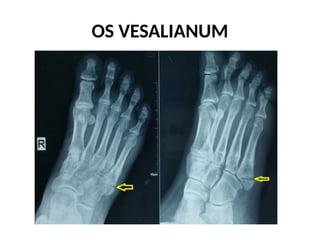

OS VESALIANUM